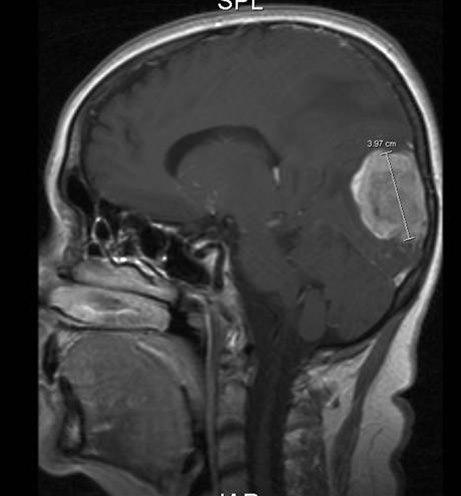

Hjernesvulst er en svulst som oppstår i hjernen. Det finnes mange ulike typer hjernesvulster. Noen har en god prognose, andre dårlig. Noen vokser svært langsomt, andre vokser hurtig. En viktig oppgave er derfor å få en nøyaktig diagnose.

Hjernesvulst er en svulst som oppstår i hjernen. Svulster er celleklumper som består av celler som deler seg og vokser raskere enn normalt vev. Dersom veksten er ukontrollert og svulsten vokser inn i det omgivende vevet (infiltrerer) og kan spre seg til andre områder av kroppen, foreligger en ondartet (malign) svulst. Svulster som har spredt seg til hjernen fra andre deler av kroppen (hjernemetastaser), omtales ikke her.

Det finnes mange ulike typer hjernesvulster. De deles inn etter hvilken celletype de minner mest om, hvor i hjernen de er lokalisert og hvorvidt de er godartet eller ondartet. Fordi hjernesvulster som er godartet kan være dødelig på grunn av sin plassering, risikerer man at skillet mellom en godartet og ondartet svulst blir kunstig.